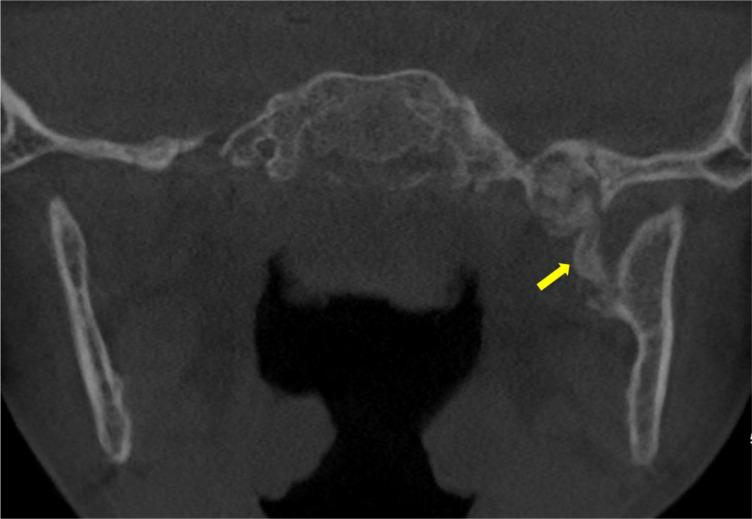

本报告报告一例非常罕见的8岁儿童,由蝶下颌韧带钙化引起的进行性限制开口(牙关)。这个病例突出了与这种疾病相关的诊断和治疗挑战的困难。我们讨论了详细的临床和放射学方法,包括用于识别钙化的成像技术,以及所选择的治疗方案,即颌面物理治疗。本报告提供了新的信息,现有文献对这种罕见的实体和提供有用的信息,临床管理类似的情况下。教学要点:蝶下颌韧带骨化症是一种非常罕见的导致张嘴受限的原因,也是一种具有挑战性的诊断。

This report aims to present a very rare case of progressive limited mouth opening (trismus) in an 8‑year‑old child caused by calcification of the sphenomandibular ligament. This case highlights the difficulty of diagnostic and therapeutic challenges associated with this disorder. We discuss the detailed clinical and radiological approach, including the imaging techniques used to identify the calcification, as well as the treatment option chosen, namely maxillofacial physiotherapy. This report provides new information to the existing literature on this rare entity and to provide useful information for the clinical management of similar cases. Teaching point: Sphenomandibular ligament ossification is a very rare cause of limitation of mouth opening and can be a challenging diagnosis.